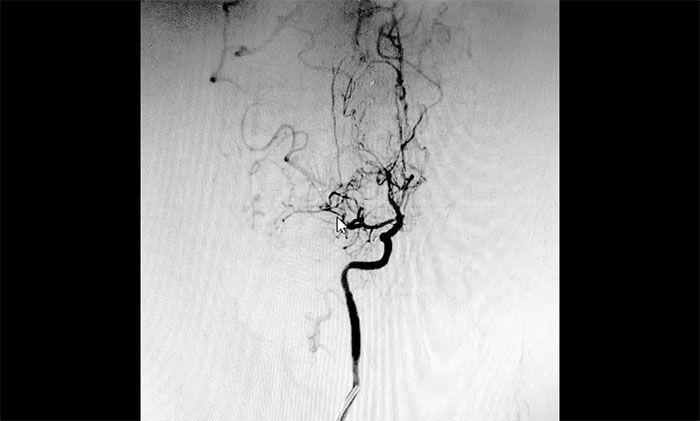

刚入院的范先生意识状态时好时坏,人非常消瘦,精神萎靡。神经外科于耀宇主任团队第一时间为其完善相关检查,DSA检查显示,患者双侧颈内动脉纤细,双侧大脑前、中动脉主干节段性狭窄,中远端分支明显减少,局部见代偿性异常血管网,符合烟雾病特征。

▲ 异常血管网形似“烟雾”